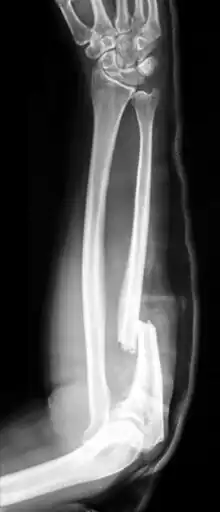

When there is a displaced fracture and also when the radioulnar joints are involved an operation is often performed, using either flexible rods or screws and plates in order to reduce the fracture and immobilise the bone.[2]

If the fracture is not displaced, is stable, and is not associated with another fracture, it may be treated with a cast for around five to six weeks.[2] During the recovery period healing can be followed up with x-rays.[2] Heavy lifting should be avoided.[2] After the cast has been removed exercises are encouraged and full strength is regained over time.[2] Treatment may also be with splinting and early movement.[1]